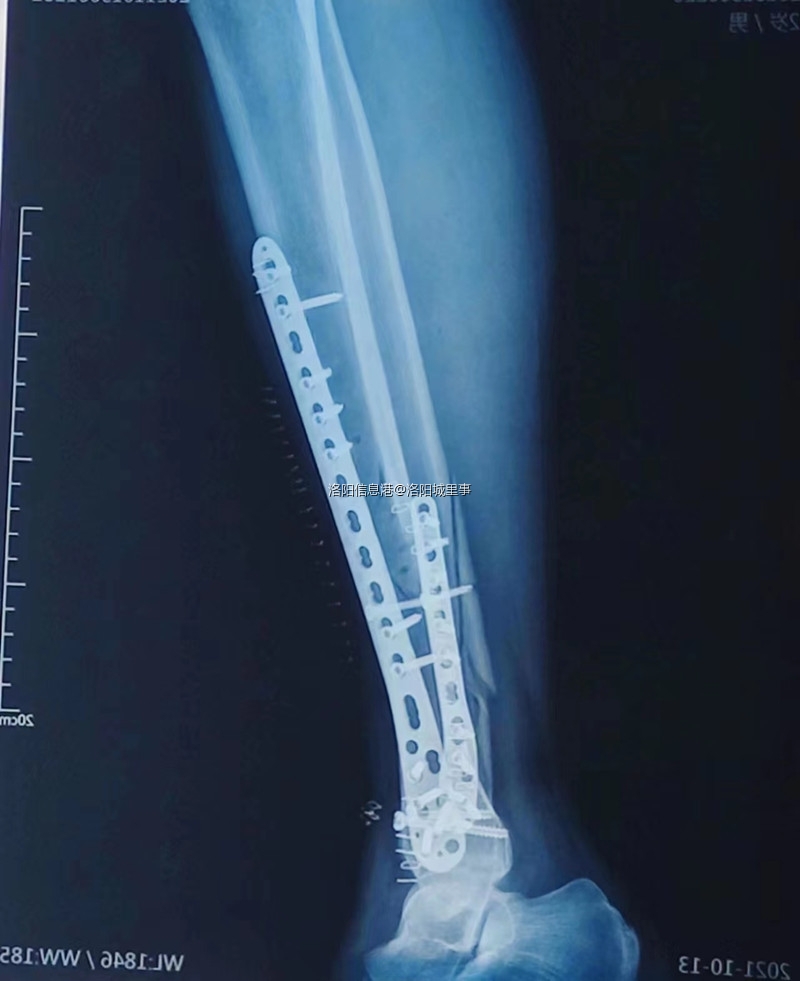

当天洛宁县120救护车将我送至洛阳市第六人民医院,经医院彩色影像诊断左小腿胫骨、腓骨完全断裂、脱离两节,并骨裂至脚踝部位,医生告知骨折情况非常严重,需手术对接断骨植入钢板固定,一年半后视情况再采取相应措施,后期面临多次手术,治疗期间以及康复期间可能产生的并发症、后遗症目前无法预料,截至2022年4月份手术至今已经半年,经拍片复查小腿腓骨仍没有完全愈合,走路步态完全不正常,有明显的陂行状态。